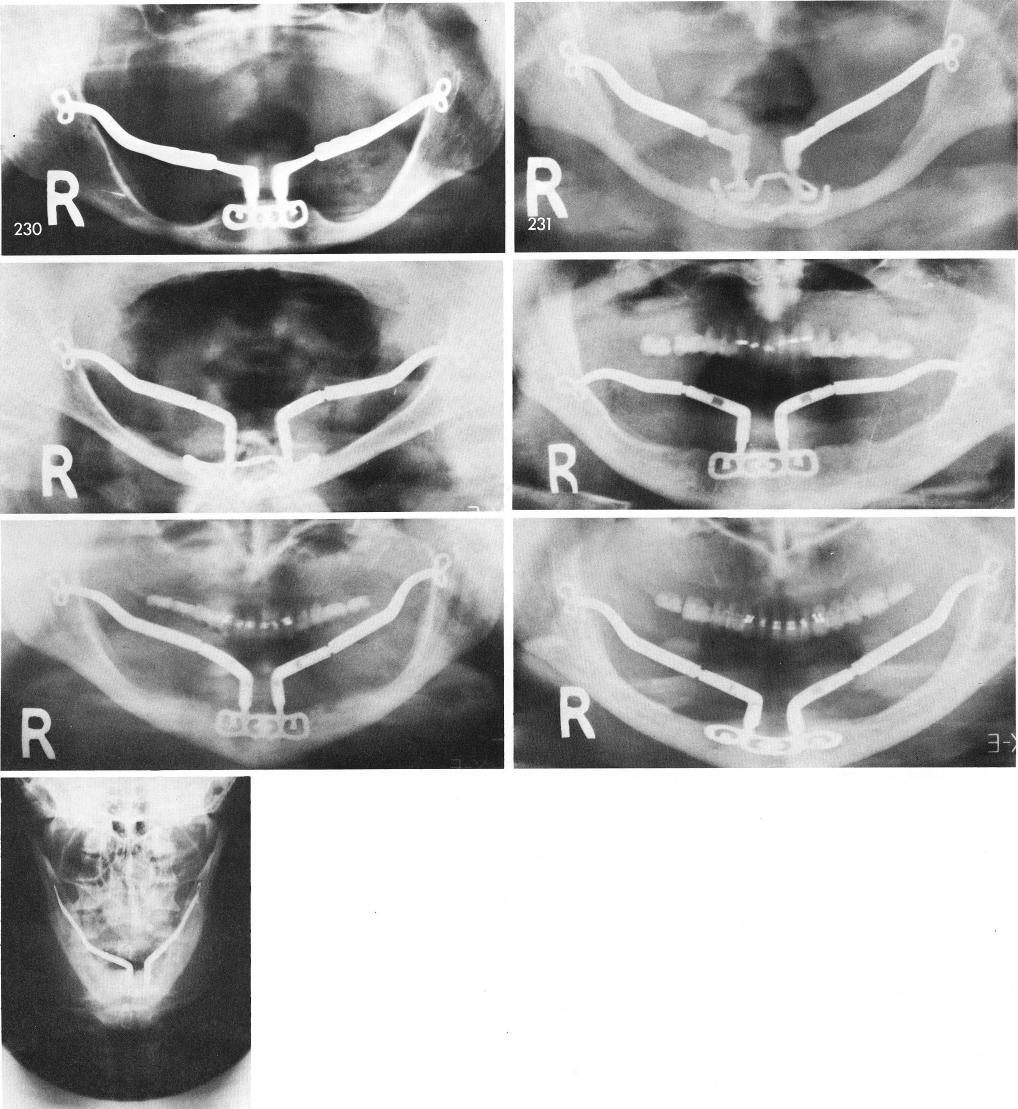

1 X rays showing five piece symphyseal ramus system